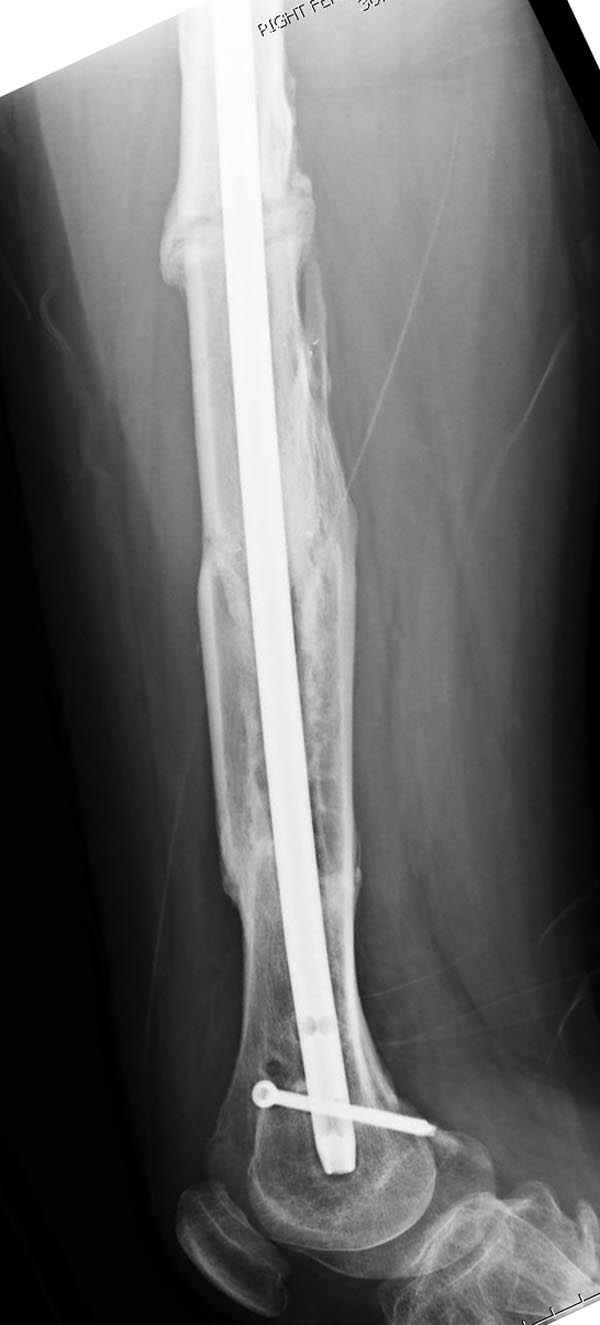

Инфекция канала и стрессовый перелом:

Представляю снимки больного с политравмой: леченного в другом мед.учреждении по поводу открытого перелома бедра, сперва аппаратом наружной фиксации, затем пластиной. Обратился к нам через 8 месяцев после удаления пластины с проблемой несросщего перелома бедренной кости, без клинических проявлении к инфицированию (не все снимки сохранены)

Рутинный интрамедуллярный остеосинтез с расверливанием и с фиксацией реконструктивным трокантерик штифтом (рис №1, №2),

если первые 4 месяца послеоперационного периода проходил без проблем, но на 5 месяце появились боли в дистальном отделе бедра и температура, т.е. симптомы медуллярного инфицирования (рис №3, №4).

При обзоре причин перелома, на снимке №2 обнаружили, что один из стержней аппарата наружной фиксации проходил только через передний кортекальный слой, что создало стрессовую зону на бедре и в результате перелом из-за незначительной травмы.

На снимке N2 виден канал от стержня во фронтальной плоскости, на уровне которого на снимке N7 уже перелом.